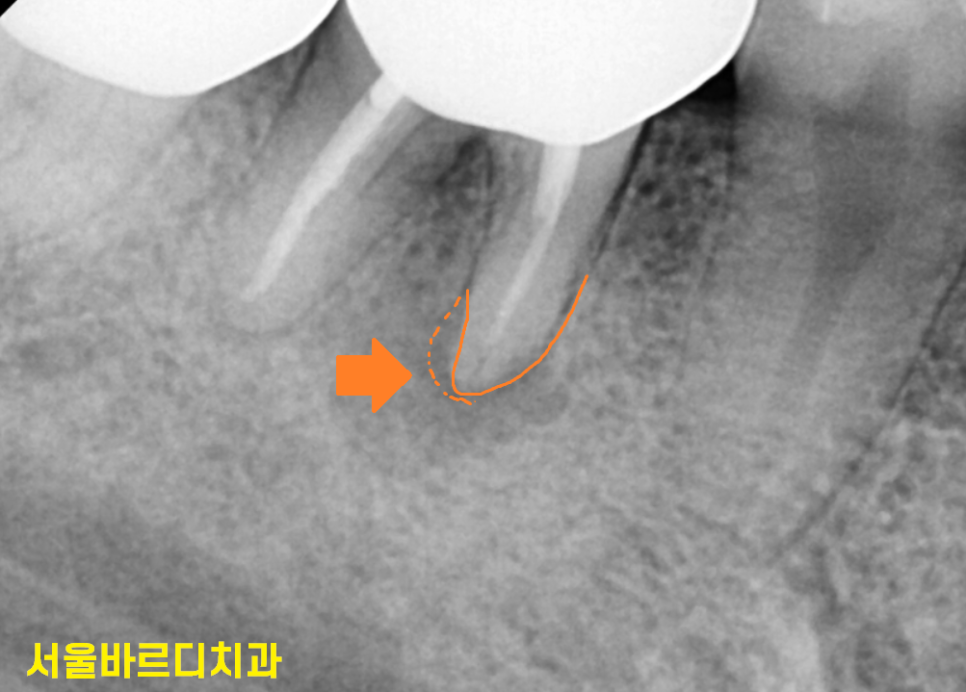

역시나 치아 뿌리 끝 염증으로

주변 뼈가 녹은게 관찰됩니다.

염증이 커지면 물혹처럼 잇몸이 부풀어오르셨네요.

그냥 잇몸 물집이 생겼을 리가 없습니다.

해당 치아도 신경치료를 했네요~

치아 신경 내부가 오염되거나

잇몸 주변 염증이 생겼거나

세균 감염 등으로

고름이 생깁니다.